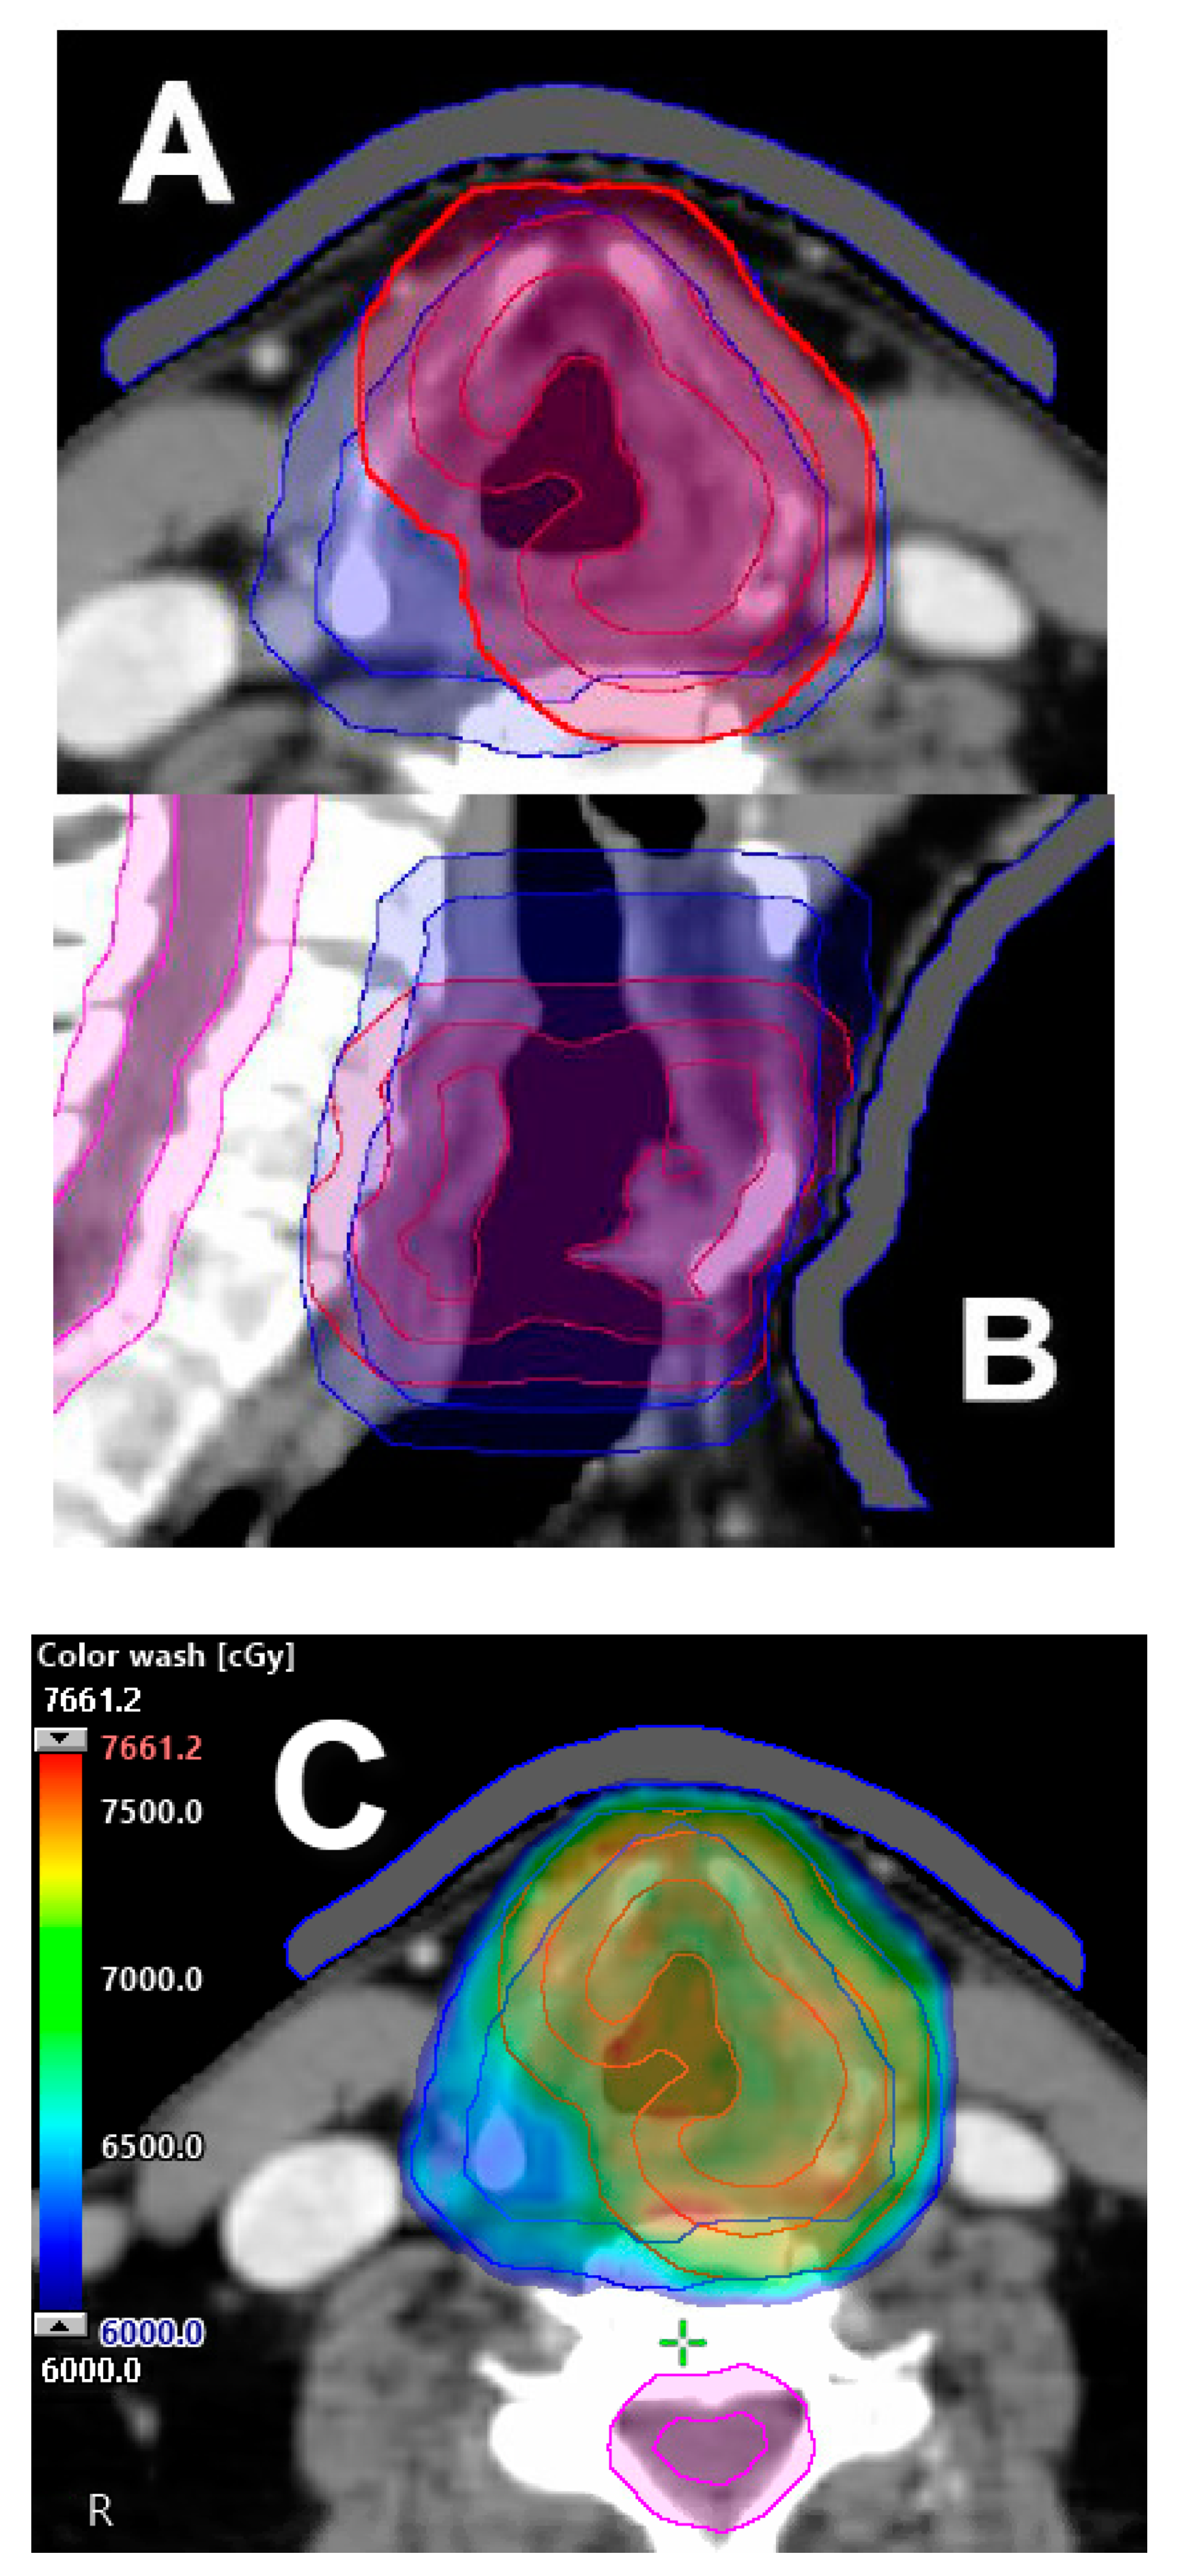

- De Veij Mestdagh, P.D.; Jonker, M.C.J.; Vogel, W.V.; Schreuder, W.H.; Donswijk, M.L.; Klop, W.M.C.; Al-Mamgani, A. SPECT/CT-guided lymph drainage mapping for the planning of unilateral elective nodal irradiation in head and neck squamous cell carcinoma. Eur. Arch. Otorhinolaryngol. 2018, 275, 2135–2144. [Google Scholar] [CrossRef] [PubMed]

- De Veij Mestdagh, P.D.; Janssen, T.; Lamers, E.; Carbaat, C.; Hamming-Vrieze, O.; Vogel, W.V.; Sonke, J.J.; Al-Mamgani, A. SPECT/CT-guided elective nodal irradiation for head and neck cancer: Estimation of clinical benefits using NTCP models. Radiother. Oncol. 2019, 130, 18–24. [Google Scholar] [CrossRef] [PubMed]

- De Veij Mestdagh Walraven, I.; Vogel, W.V.; Schreuder, W.H.; Van Werkhoven, E.; Carbaat, C.; Donswijk, M.L.; Van Den Brekel, M.W.M.; Al-Mamgani, A. SPECT/CT-guided elective nodal irradiation for head and neck cancer is oncologically safe and less toxic: A potentially practice-changing approach. Radiother. Oncol. 2020, 147, 56–63. [Google Scholar] [CrossRef] [PubMed]